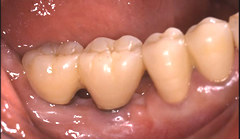

人工歯を支えるためのアバットメント(支台部)をインプラントに接続します。 歯肉が治癒するまで約3週間待ちます。仮歯あり。